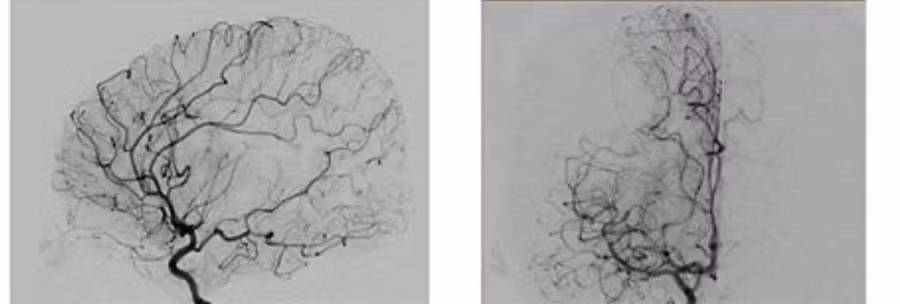

Hình ảnh động mạch sau khi được can thiệp.